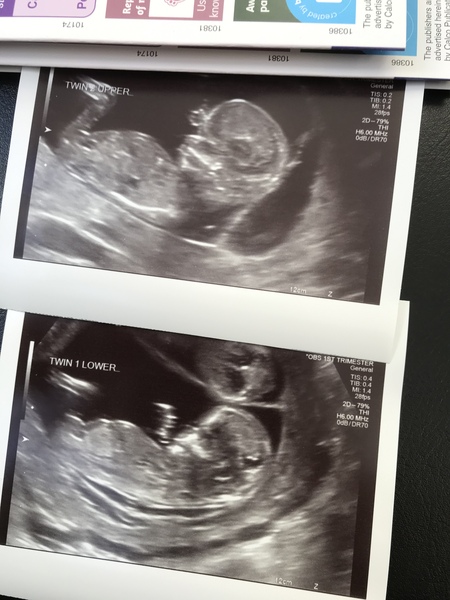

Runningbutnotscared · 14/02/2019 16:08

12 week scan! I can’t wait to find out the sexes, I can take no more surprises.

@Runningbutnotscared lovely scan pics, so jealous that you're having twins!!

@Runningbutnotscared wonderful piccies! do twins run in your family? X